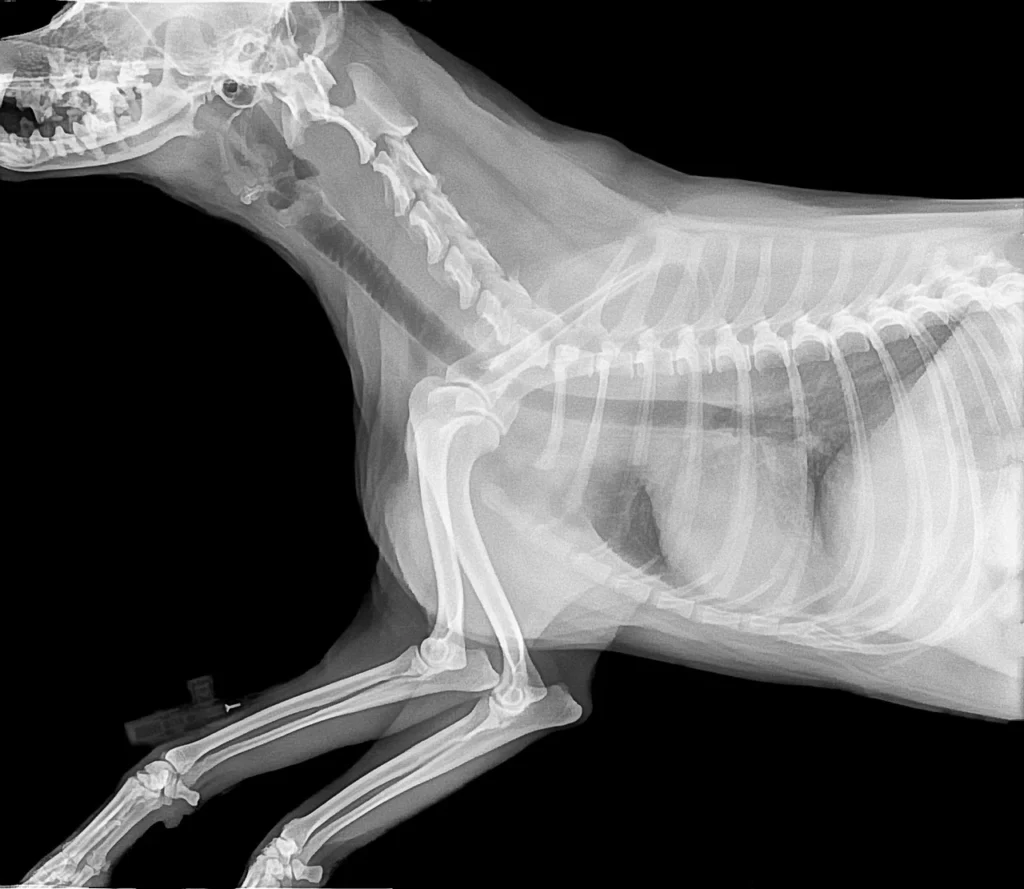

A röntgenvizsgálat az állatorvoslás egyik legfontosabb diagnosztikai eszköze. Segítségével olyan elváltozásokat fedezhetünk fel, amelyek alap fizikális vizsgálattal nem láthatók. A röntgenvizsgálat fájdalommentes, gyors és pontos képet ad kedvence egészségi állapotáról.

Mellkasi elváltozások

- Szívbetegségek és szívnagyobbodás

- Légzőszervi problémák (tüdőgyulladás, hörgőgyulladás, légcsőszűkület)

- Folyadékgyülem a mellkasban

- Mellűri daganatok felismerése

- Csonttörések és repedések kimutatása

- Ízületi betegségek (arthritis, csípődiszplázia)

- Gerincproblémák és porckorongsérvek

- Idegentestek a lábban vagy testben